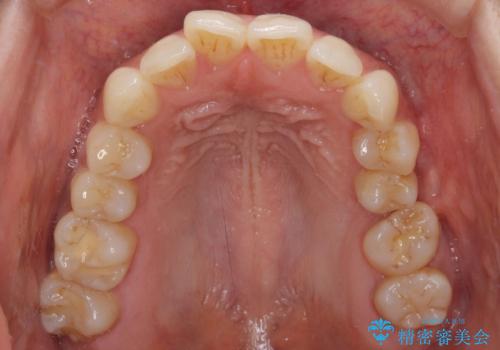

インビザライン矯正で全体の歯列と整えるとともに、左上第一大臼歯部にはスペースを作り、インプラントによる補綴治療を行うこととしました。

歯の傾斜が改善され、インプラントによるクラウンが装着されたことで、物が挟まることもなくなりました。